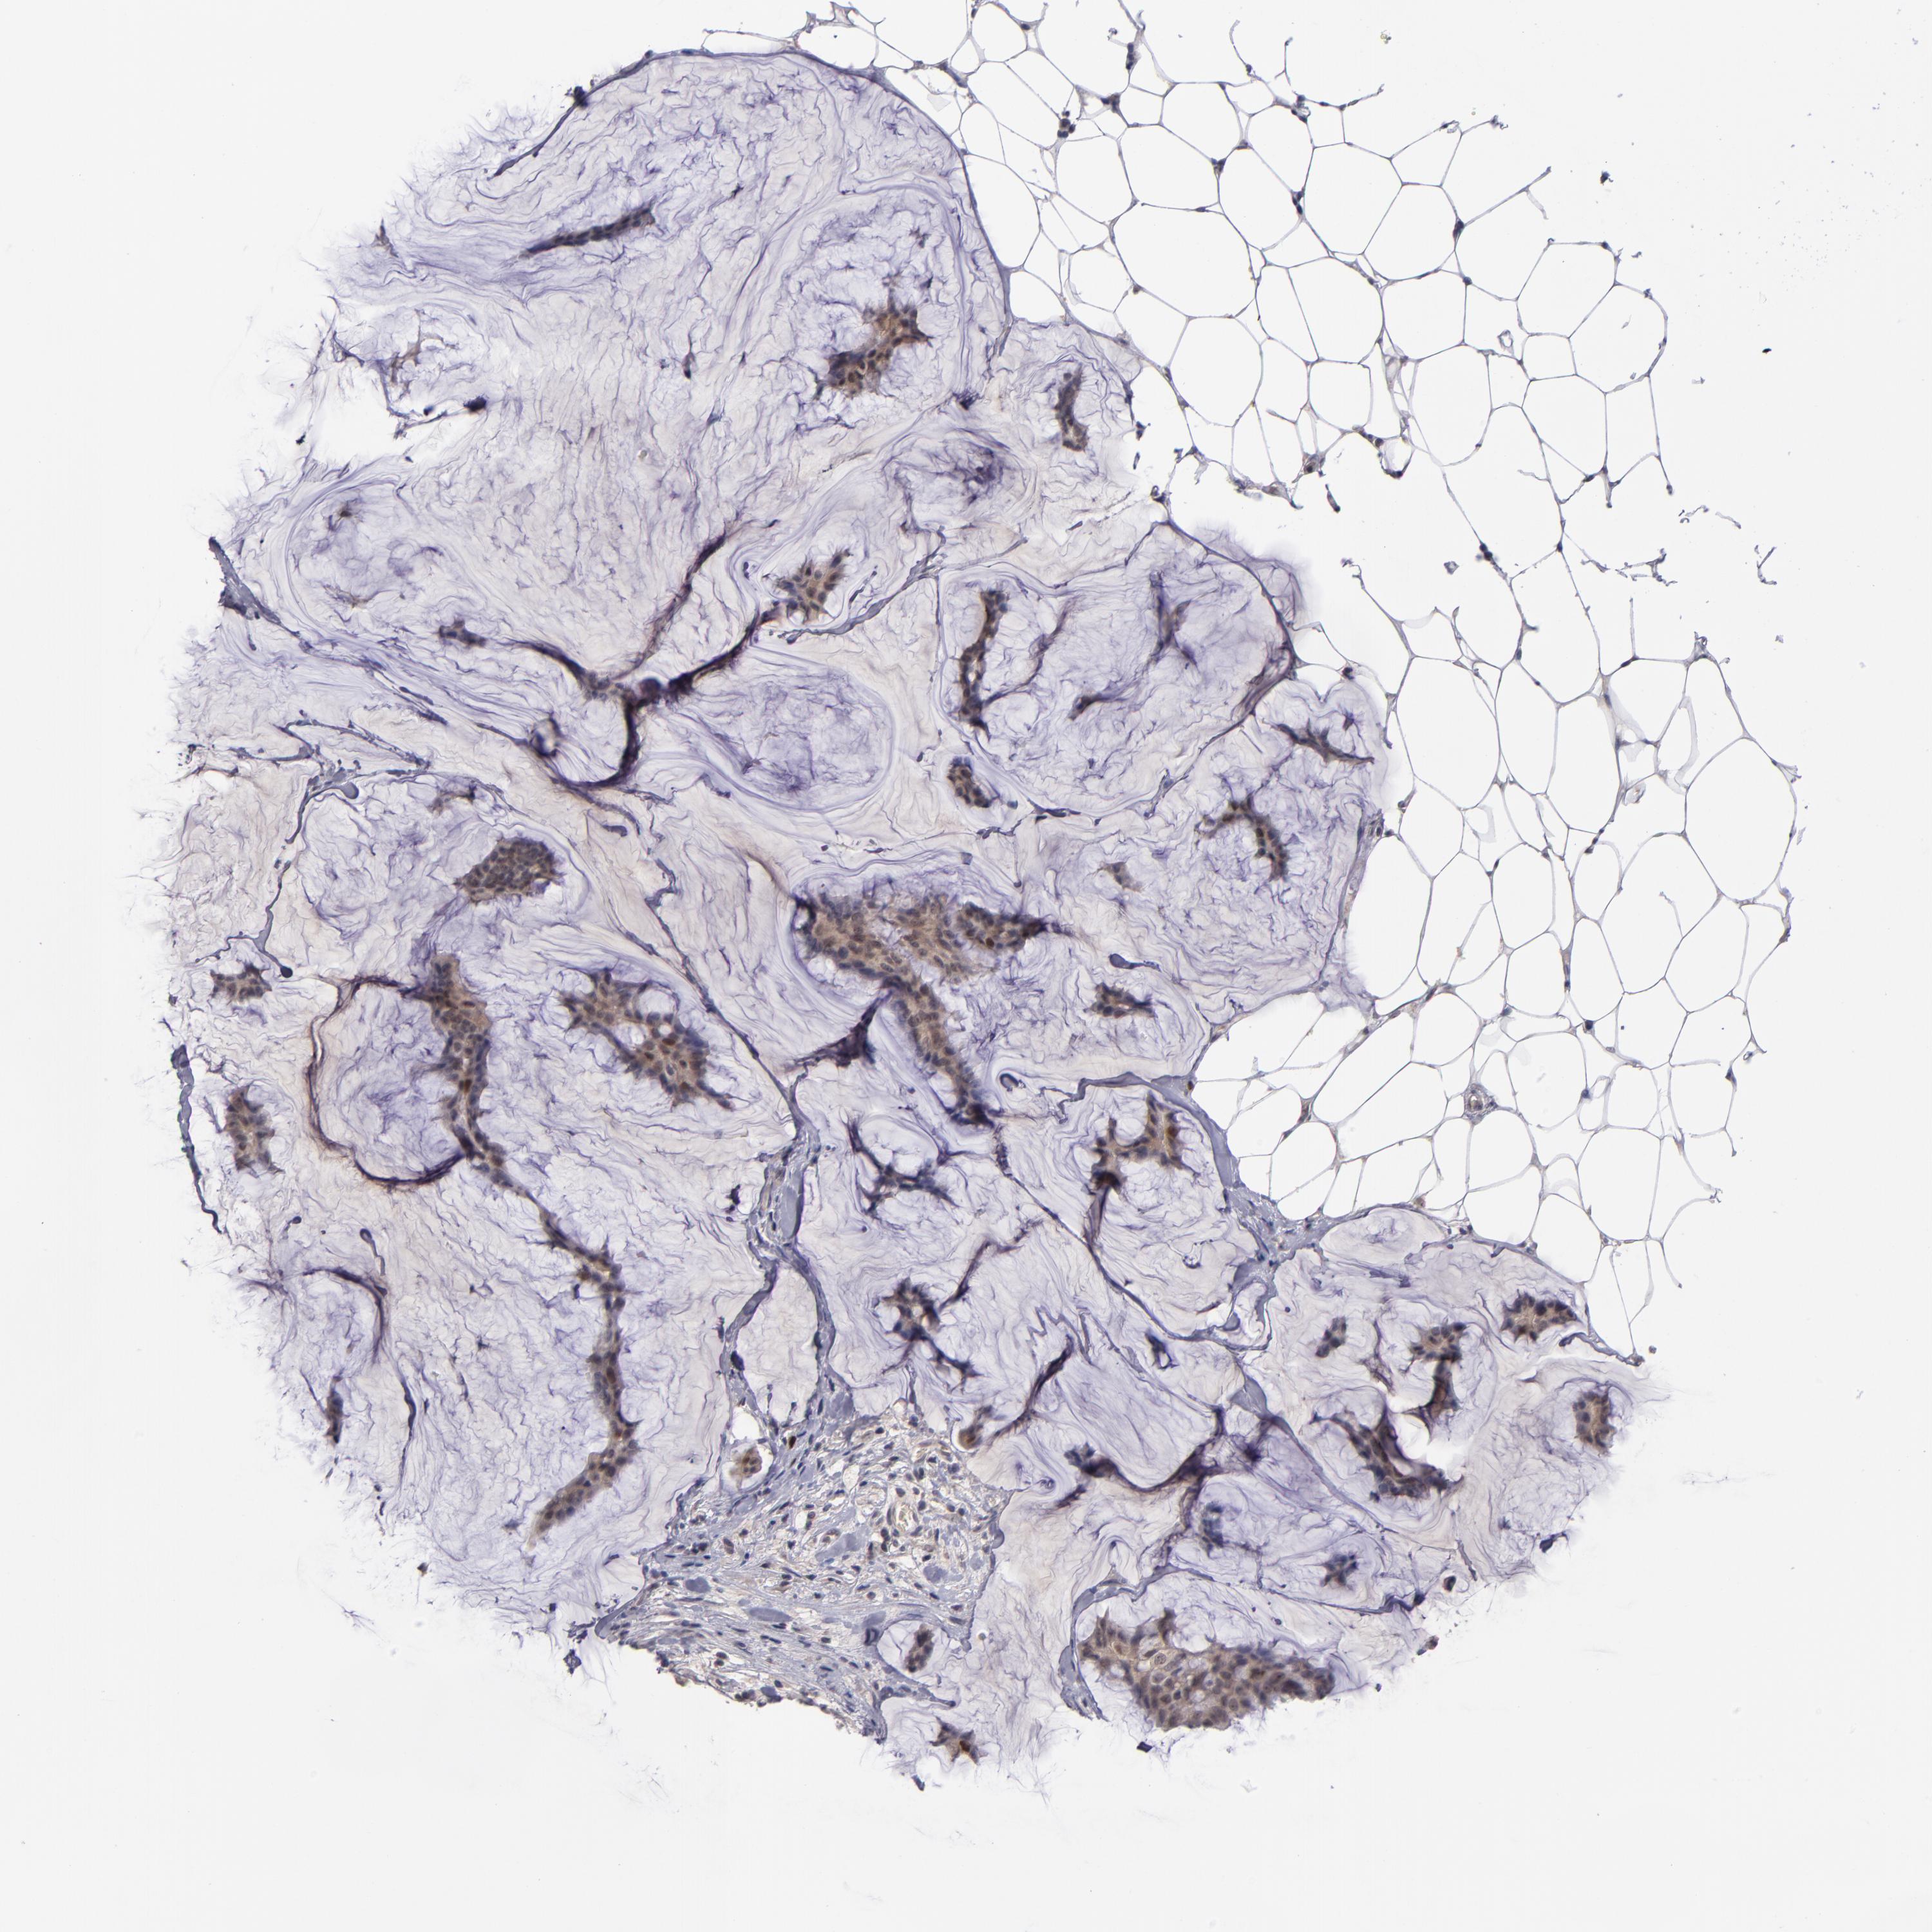

CANCER BREAST CANCER Show tissue menu

BRCA TCGA BRCA VALIDATION PROTEIN EXPRESSION

ANTIBODIES

AND

VALIDATION